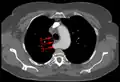

Aberrant subclavian artery at axial CT-scan. (1) trachea, (2) esophagus, (3) Aberrant subclavian artery.